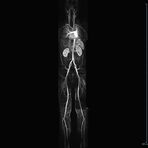

MR-Angiografie (MRA)

Ganzkörper Angiographie mit Kontrastmittel

• MR-Angiographie mit Kontrastmittel

• Erfassung arterieller und venöser Gefäße/Bypässe aller Körperregionen mit 3D-Rekonstruktion

• je nach klinischer Fragestellung zeitaufgelöste MR-Angiographie (4D-MRA) z.B. bei Frage arteriovenöse Fistel/ Shunt oder Darstellung Unterschenkelarterien vor geplanter Bypassoperation.